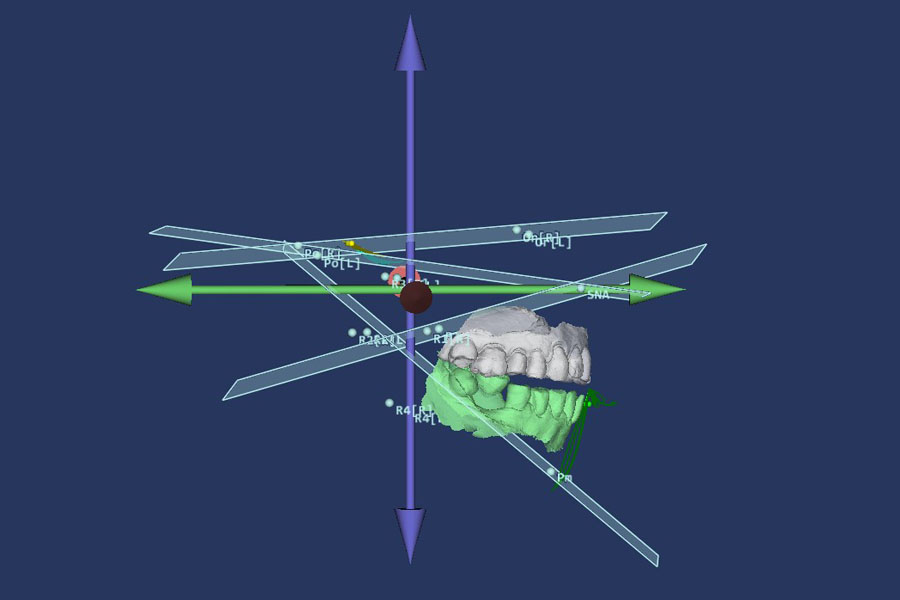

Allows you to work with dynamic data, virtual models, and CBCT data. You can visualize occlusal contacts and all dynamic abnormalities. Using CBCT data, you can determine the bite height and identify joint dysfunctions. You get a virtual patient.

Record axiography, make face and tooth scans, import CBCT

Merge all data into one 3D model. See all in real-time animation

Set new jaw place, calculate future position of a jaw. AI will assist you with it

Export whatever you need: CT, tracks, planes with your custom parameters